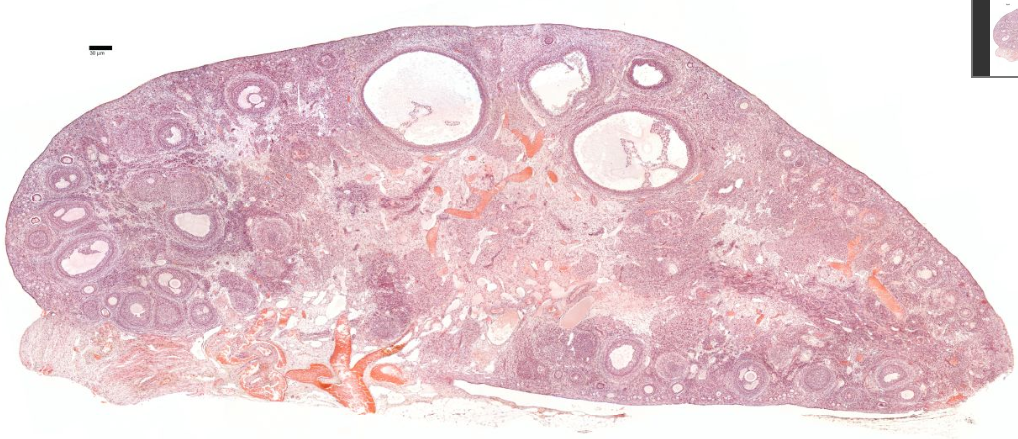

{A diagram of a sectioned ovary (a) shows the different stages of follicle maturation, ovulation, and corpus luteum formation and degeneration. All of the stages and structures shown in this diagram actually would appear at different times during the ovarian cycle and do not occur simultaneously. Follicles are arranged here for easy comparisons. The primordial follicles shown are greatly enlarged. The histologic sections identify primordial follicles (b), a primary follicle (c), a secondary follicle (d), and a large vesicular follicle (e). After ovulation, the portion of the follicle left behind forms the corpus luteum (f), which then degenerates into the corpus albicans (g). All H&E.]

Next is a cortex where the ovarian follicles can be found.

Ovarian follicles are oocytes surrounded by epithelial cells.

Included in the follicles are the cumulus oophorus, membrana granulosa, and the granulosa cells inside it, corona radiata, zona pellucida, and primary oocyte.

The zona pellucida, theca of follicle, antrum and liquor folliculi are also contained in the follicle. Also in the cortex is the corpus luteum derived from the follicles.